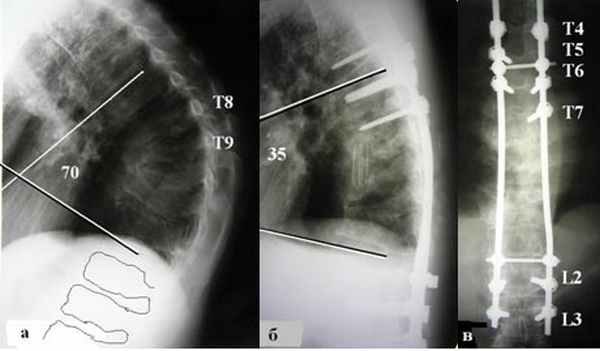

Корригирующие операции при кифотической деформации

а) и б) пологая кифотическая деформация грудного отдела позвоночника - 86° после перенесенной болезни Шейермана-Мау.

а) тотальная деструкция Th6- Th7-Th8 (туб. спондилитTh6- Th7-Th8);

б) удаление телTh6-Th7-Th8 позвонков боковой спондилодез мешем с ауторебром;

В) транспедикулярнаяфиксацияTh3- Th4-Th5-Th10- Th11 позвонков.